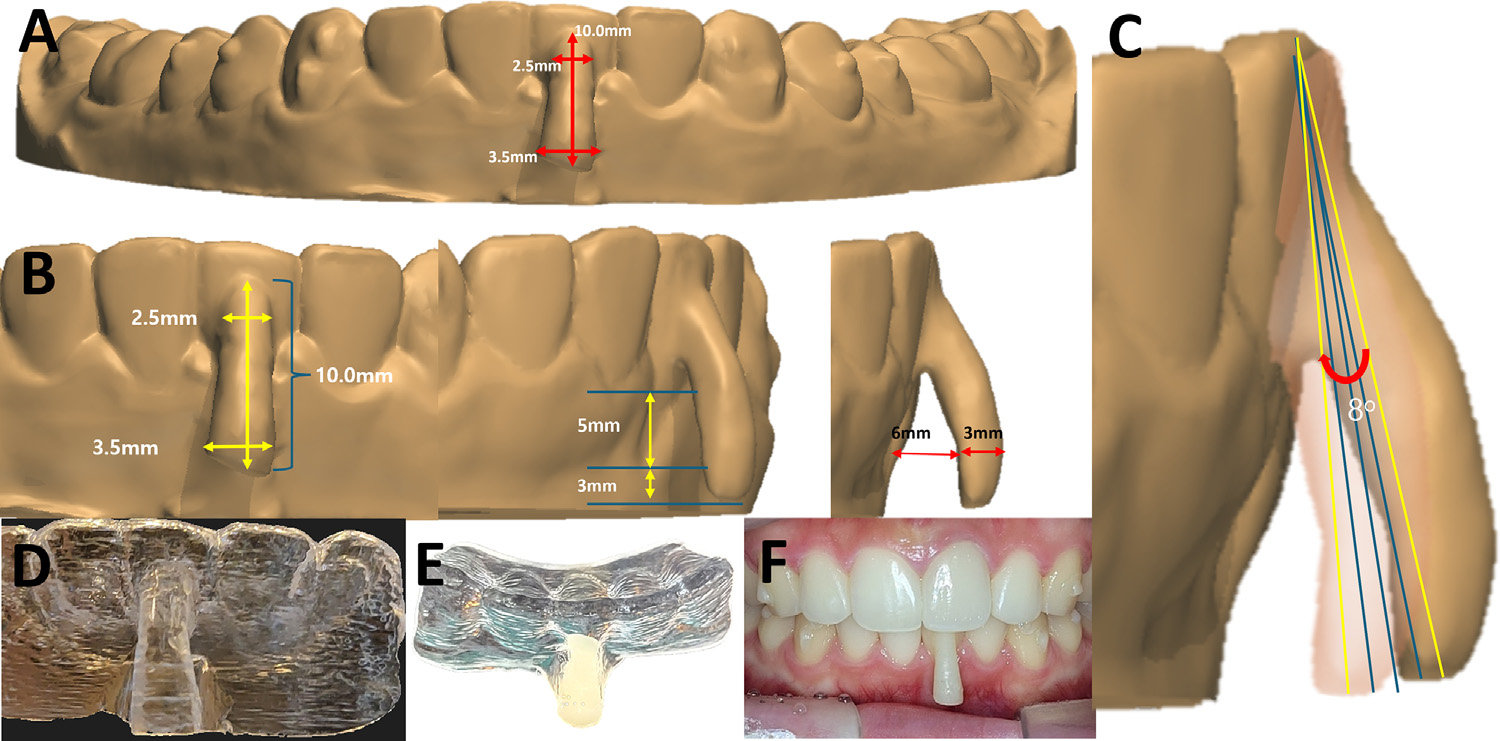

투명교정 전문기업 시스루테크㈜의 홍경재 대표가 개발한 시스루 얼라이너 ‘오버행잉 어태치먼트(Overhanging Attachment)’ 기술이 세계 교정학계의 주목을 받고 있다.

홍 대표는 해당 기술을 활용해 수술 없이 잇몸퇴축(gingival recession)을 회복시키는 데 성공했으며, 이 연구 결과는 미국 교정학회 공식 학술지 ‘American Journal of Orthodontics and Dentofacial Orthopedics Clinical Companion (AJO-DO Clinical Companion)’ 2025년 10월호에 게재됐다.

이번 논문은 국내 최초로 투명교정만으로 퇴축된 잇몸을 재생시킨 임상 보고로, 하악 전치부에서 5mm의 잇몸퇴축이 11개월간의 교정치료 후 1mm로 회복되는 임상 결과를 확인했다. 치조골과 잇몸조직이 자연스럽게 복원되는 과정을 객관적 데이터로 제시했다는 점에서 의미가 크다.

‘오버행잉 어태치먼트’는 치근 이동 시 발생하는 토크(torque)를 정밀 제어해, 치아의 중심저항점(center of resistance)에 가까운 위치에서 힘을 전달하도록 설계됐다. 이를 통해 정확한 치체이동(root movement)이 가능해지고, 결과적으로 잇몸재생이 유도된다.

공동저자로는 미국 A.T. Still University의 박재현 교수가 참여했으며, 해당 기술은 국내외 특허 등록을 완료했다. 이번 성과는 한국 디지털 치의학 기술이 국제 학술무대에서 인정받은 사례로 평가된다.